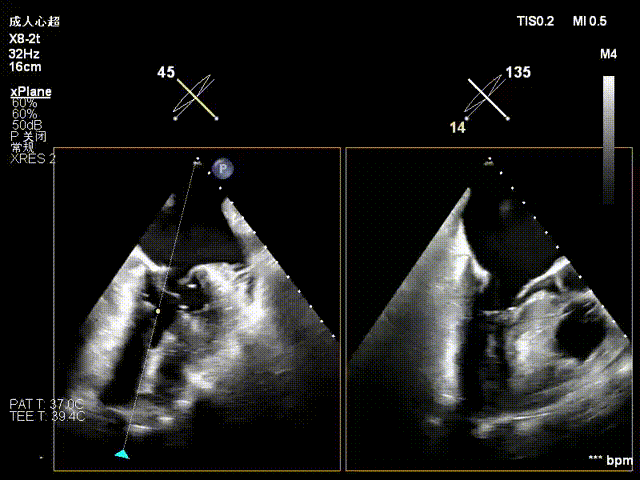

在左房打开上夹

调整好夹子位置钟向后,在左室打开下夹,捕获夹合瓣叶

将夹子收入闭合环

评估夹合效果